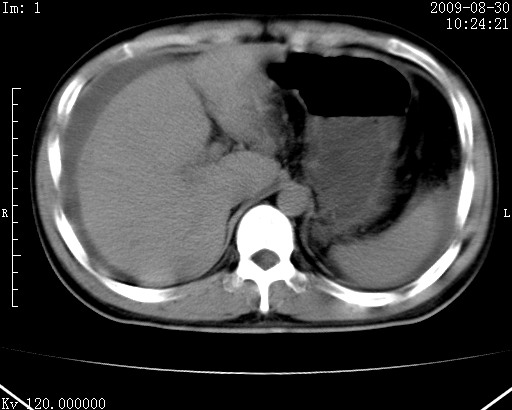

患者唐某,男31岁,已婚,本地务农。

自述入院前两天一次进食较多冷饮之后,出现阵发性上腹部疼痛,次日加剧伴恶心、呕吐,呕吐后症状稍减轻。食欲差。大便每天1-2次,量少,暗红色水样。小便赤。无畏寒、发热、咳嗽等呼吸道症状。无高血压及胃病史。

检查:体温、血压及脉搏正常.皮肤无黄染,浅表无淋巴结肿大。左腹肌紧张,左上腹有压痛,无反跳痛,可触及包块。

生化:钾、钠、氯、钙、ph正常,总胆红素和直接胆红素稍高,空腹血糖稍高。

尿淀粉酶:1256 u/l(正常60-401)。

血常规:wbc 22.4x109/l gr88% ly9.6%其余基本正常。

胃镜:急性胃炎。立位腹平片:未见异常。

下面是ct平扫,降结肠内是对比剂。

术前影像诊断:上段空肠急性缺血性坏死并腹水。建议手术治疗。

术中见上段空肠约70cm长范围坏死,从屈氏韧带远端约10cm处开始。坏死肠管肿胀变形变色,管壁明显环形增厚,部分聚成大肿块,无扭转和套叠。肠系膜上动脉分支内广泛泥沙状血栓。肠切除。

临床诊断:肠系膜上动脉梗塞并急性肠坏死。

开始时我们科也有人认为是套叠,最后统一意见,不考虑肠套。我们看到的“靶征”,“晕圈征”,“双圈征”实际上只是单根肠管的横断面。坏死肿胀后肠壁各层的密度不一样。

左侧腹小肠腔管壁明显增厚,部分内示靶征,走行异常,部分肠系膜绳样改变,肝包膜下及肠间较多液体密度,然梗阻近端肠腔积气不明显。

考虑;肠扭曲伴肠坏死。

腹部肠管肠管弥漫性增厚、肿胀,考虑为肠管缺血或淤血改变,未排除空肠管坏死。腹水。

有结果了,回顾分析,套叠只会在局部出现同心圆征,不会很长一段肠管都有,还是水肿坏死。